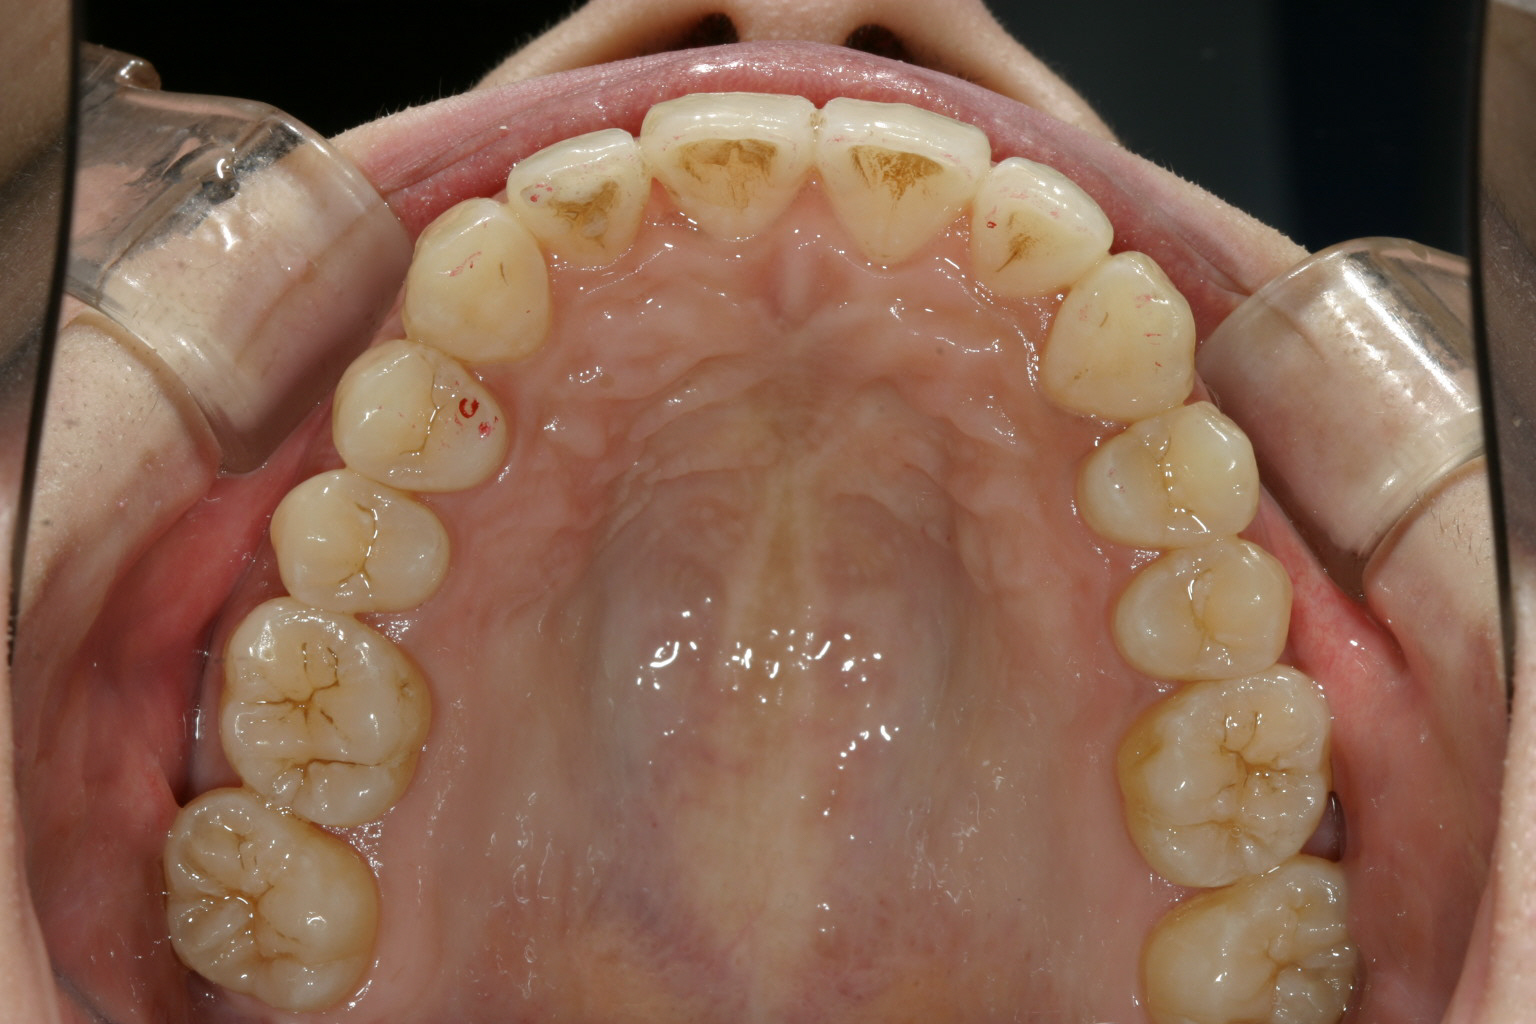

前歯が飛び出てねじれています。

かなり古い症例で先ずリンガルアーチにてアーチの拡大と前歯の叢生 治療から始めました。

リンガルアーチ後インビザラインにて治療を引き継ぎました。 綺麗に改善出来ています。